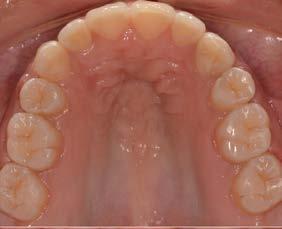

Figura 2. Planeación en tomografía axial computarizada: a) vista sagital, b) vista transversal, c) vista 360°, d) reconstrucción 3D y e) ortopantomografía.

Se creó un mapeo óseo para evaluar las dimensiones de altura y anchura ósea disponibles para la colocación del implante dental y su posterior restauración protésica. El análisis reveló una cantidad reducida de tejido óseo en el piso del seno maxilar (3.61 mm), lo que condicionó la planificación del procedimiento. Para la rehabilitación implantológica, se requiere la colocación de un

implante de al menos 8 mm de altura por 5 mm de diámetro, con adecuado espacio vestíbulo-palatino e interoclusal. No obstante, luego de considerar la insuficiencia de volumen óseo en sentido vertical y el grado de neumatización del seno maxilar, se determinó que la colocación del implante mediante técnicas convencionales no era viable, por ello la necesidad de procedimientos de aumento óseo para lograr una rehabilitación adecuada (Figura 2).